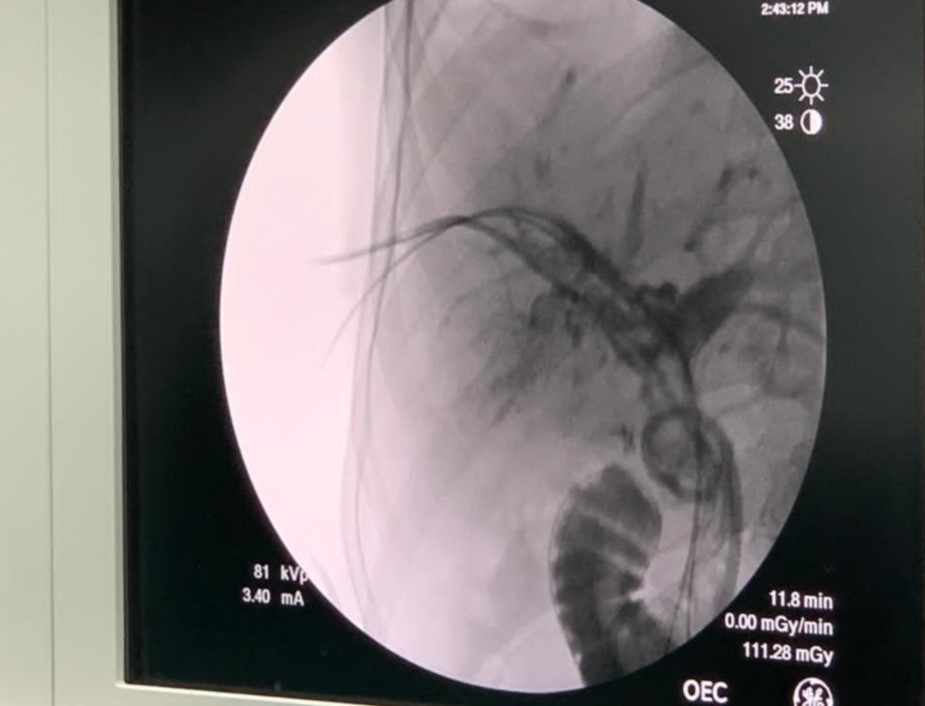

حيث قام الفريق بإزالة الحصوات الموجودة داخل الكبد (Intrahepatic biliary ducts) عن طريق الاشعة التداخلية بتقنية "التقابل" عن طريق الجلد دون الحاجة للتدخل الجراحي والدخول إلى قنوات الكبد بعد اجراء عمليات توسيع على ثلاثة مراحل تحت التخدير الموضعي في أول مرتين وإزالة الحصوات من القنوات المرارية خارج الكبد(Extrahepatic biliary ducts) باستخدام مناظير القنوات المرارية عن طريق الفم (ERCP) دون الحاجة نهائياً للجوء الى الجراحة التقليدية او الجراحة بالمنظار.